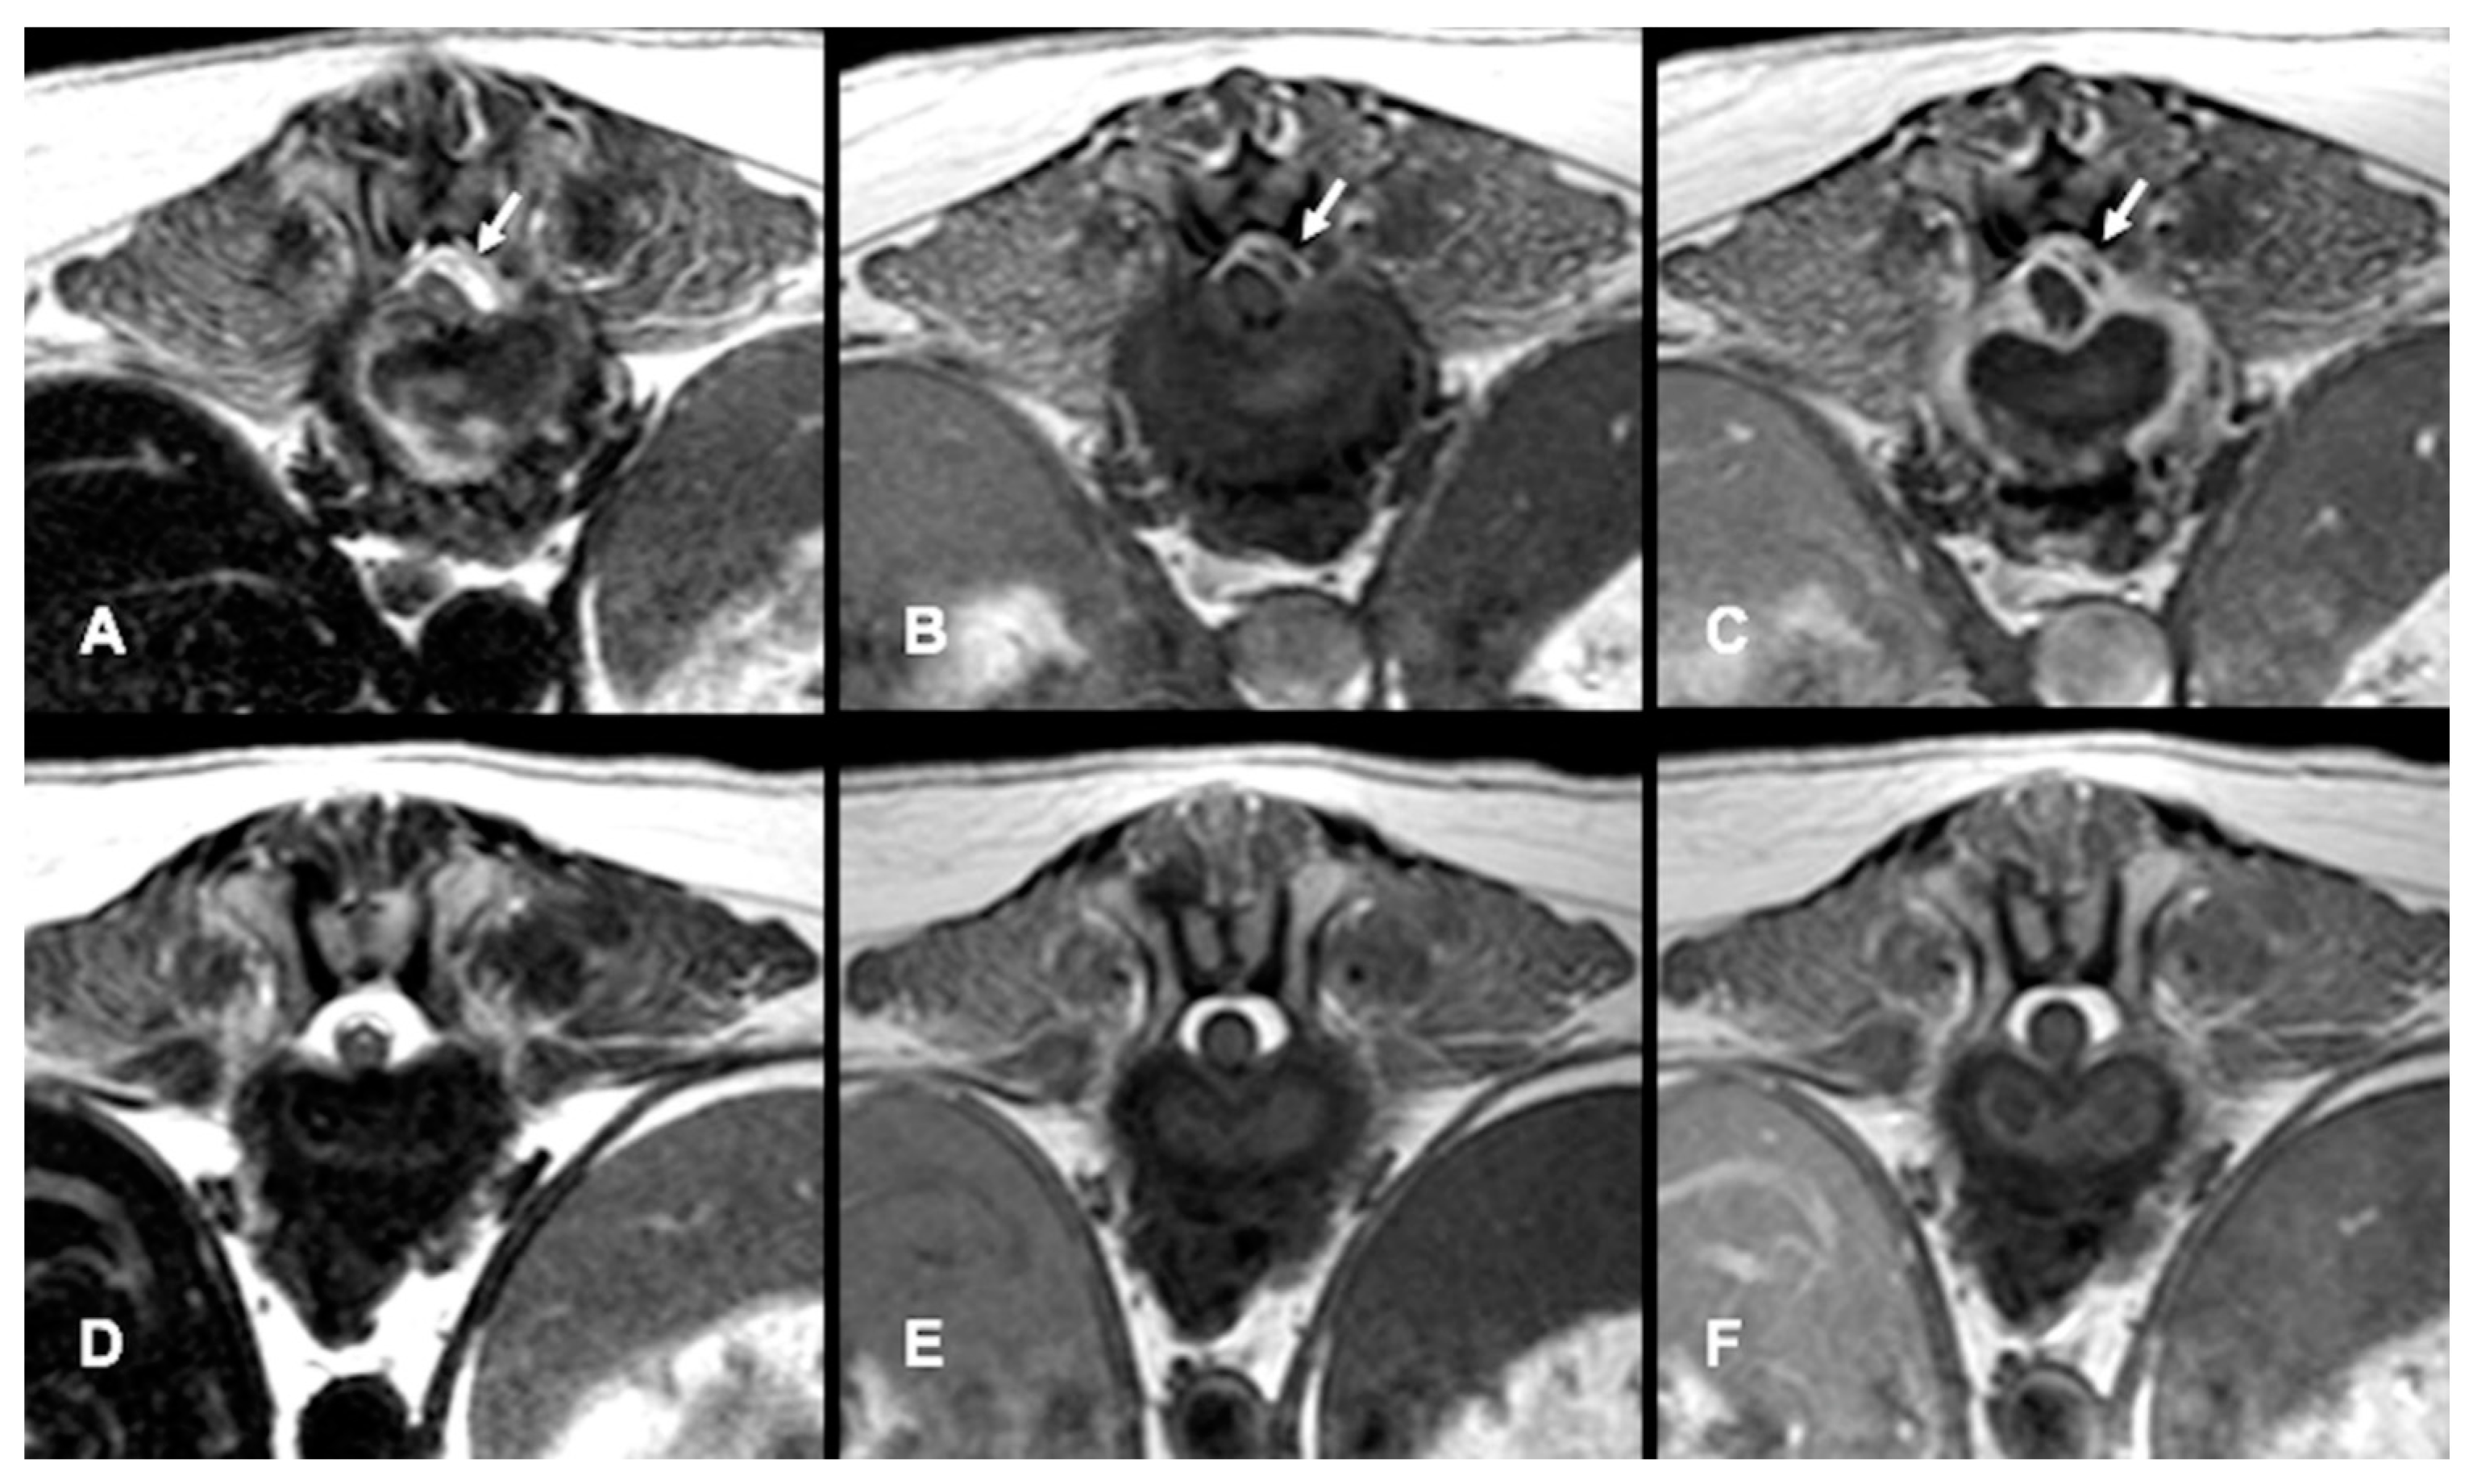

All dogs had an MRI of the spine within 24 h of presentation (Figure 1A–C, Figure 2A and Figure 3A–D). The images revealed the presence of a space-occupying accumulation of epidural material suggestive of empyema. The epidural material was hyperintense or had a mixed (hyperintense and isointense) signal on T2W sequences compared to the spinal cord and had an iso to hypointense signal on T1W sequences. After contrast administration, enhancement was observed in all cases with variable patterns (diffuse, heterogeneous, or ring-like).

Follow-up MRI studies were performed (n = 13) from 2 to 5 months after treatment initiation, in 8/13 dogs conservatively treated (Figure 1D–F) and in 5/13 of the dogs surgically treated (Figure 2B and Figure 3E–G). Radiological improvement was noticed in all dogs, considering there were no signs of epidural material or soft tissue enhancement. Bone changes (osteoproliferation and mild contrast enhancement) were still present.

Figure 3. MRI transverse planes T2-W (A), postcontrast T1-W (B), and postcontrast fat-saturated T1-W (C) of the same dog as Figure 2, showing a left dorso-lateral epidural space-occupying lesion (arrows) in the L3–L4 intervertebral level with severe spinal cord compression. Transverse T2-W image of the same dog at L4–L5 (D) also demonstrates an infiltrative lesion that extends through the left intervertebral foramen (lower arrow) in connection with the epidural lesion (upper arrow). Follow-up transverse T1-W (E), T2-W (F) and postcontrast fat-saturated T1-W (G) images at 4 months after surgery depict the resolution of the infiltrative foraminal and post-foraminal lesions and of the epidural.